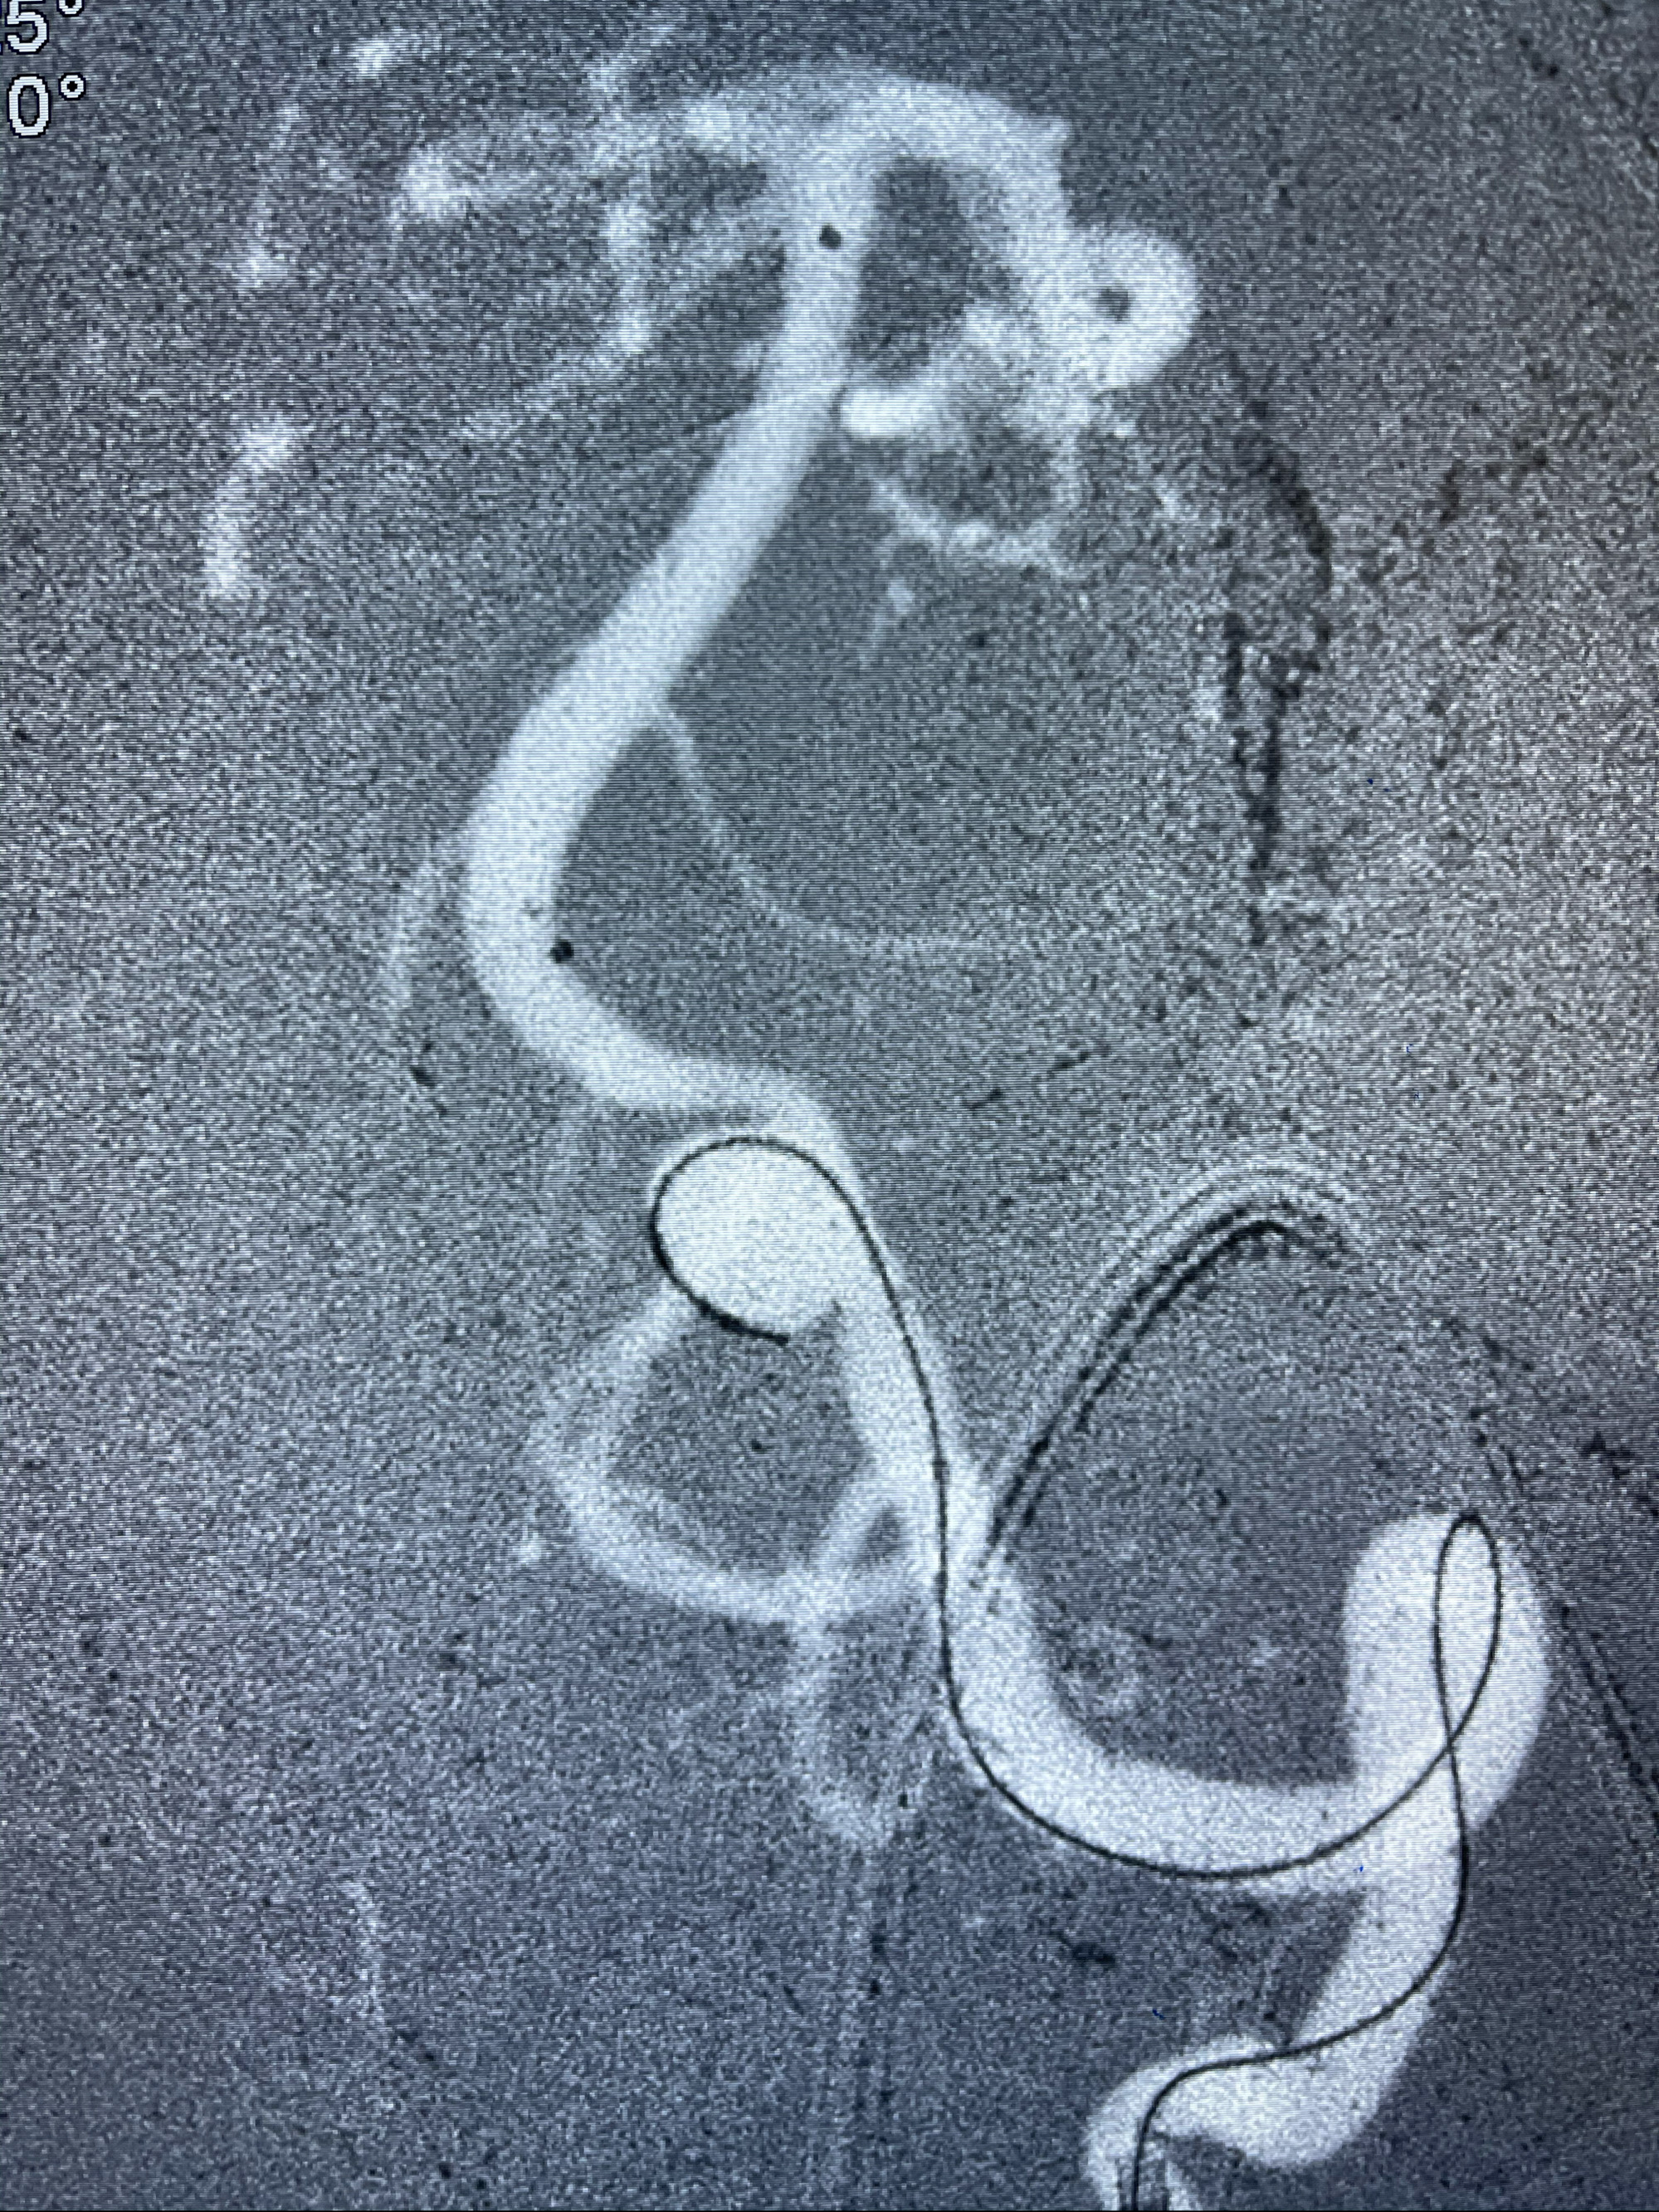

即刻造影

支架到位

支架释放,透视下